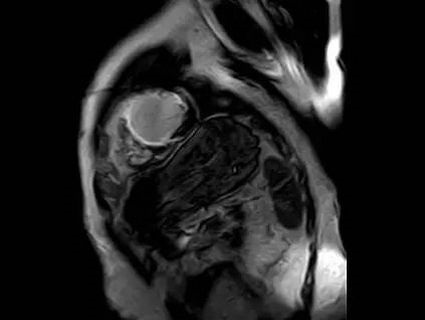

3.心肌的活动情况。比如:心肌的收缩、舒张能力的减低,局部心肌的异常活动等。

4.心肌的信号、强化是否正常。比如:炎症、水肿、纤维化、淀粉样变性、瘢痕、室壁瘤等。

3.心肌活性评估,心肌组织中失去活性的心肌细胞和延迟强化存在可靠的对应关系,即失去活性的心肌组织有延迟强化。

4.非缺血性心肌病的评估,如肥厚性心肌病、扩张性心肌病、限制性心肌病等,心肌呈现不同程度条状、斑片状、斑点状的延迟强化。

5.心肌致密化不全。